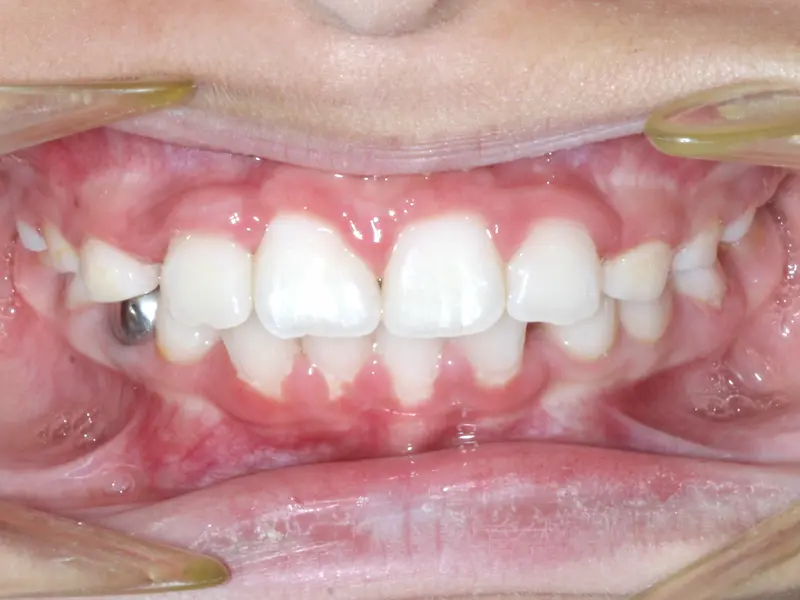

The Diagnosis

Severe crowding with blocked-out permanent teeth. The jaw size was insufficient to accommodate the erupting adult teeth, leading to significant rotation and displacement.

The Engineering

By intervening early, we utilized rapid palatal expansion to develop the arch width. This created the necessary space for the permanent teeth to erupt naturally, avoiding the need for future extractions.